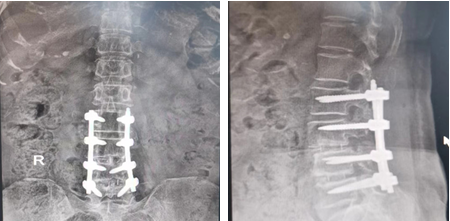

患者术后影像

后经脊柱科会诊讨论,王某符合腰椎后路椎管减压植骨融合内固定术手术指征,在韦向荣诊疗团队的密切配合下,手术过程十分顺利,术后患者症状缓解明显,患者及家属对治疗效果非常满意,患者在积极的恢复当中。